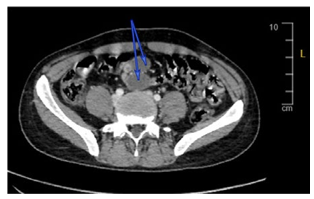

CT neck, chest, abdomen, and pelvis with IV contrast (Figure 1) showed multiple variable sized peripherally enhanced with hypodense centre enlarged (low attenuated) lymph nodes seen involving superior mediastinum (A), porta hepatis (B), superior mesenteric (C), and para-aortic lymph nodes. Figure 2 showed enlarged retroperitoneal lymph nodes suggestive of tuberculosis or leukemia.

Figure 2: Computed Tomography (CT) of the Abdomen Showing Enlarged Retroperitoneal Lymph Nodes (arrows).